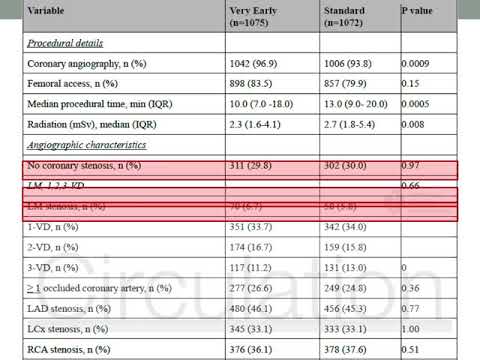

Evaluación y tratamiento invasivo temprano vs. estándar en pacientes con SCASEST. Dra. Florencia Cichello. Residencia de cardiologia. Hospital C. Argerich. Buenos Aires